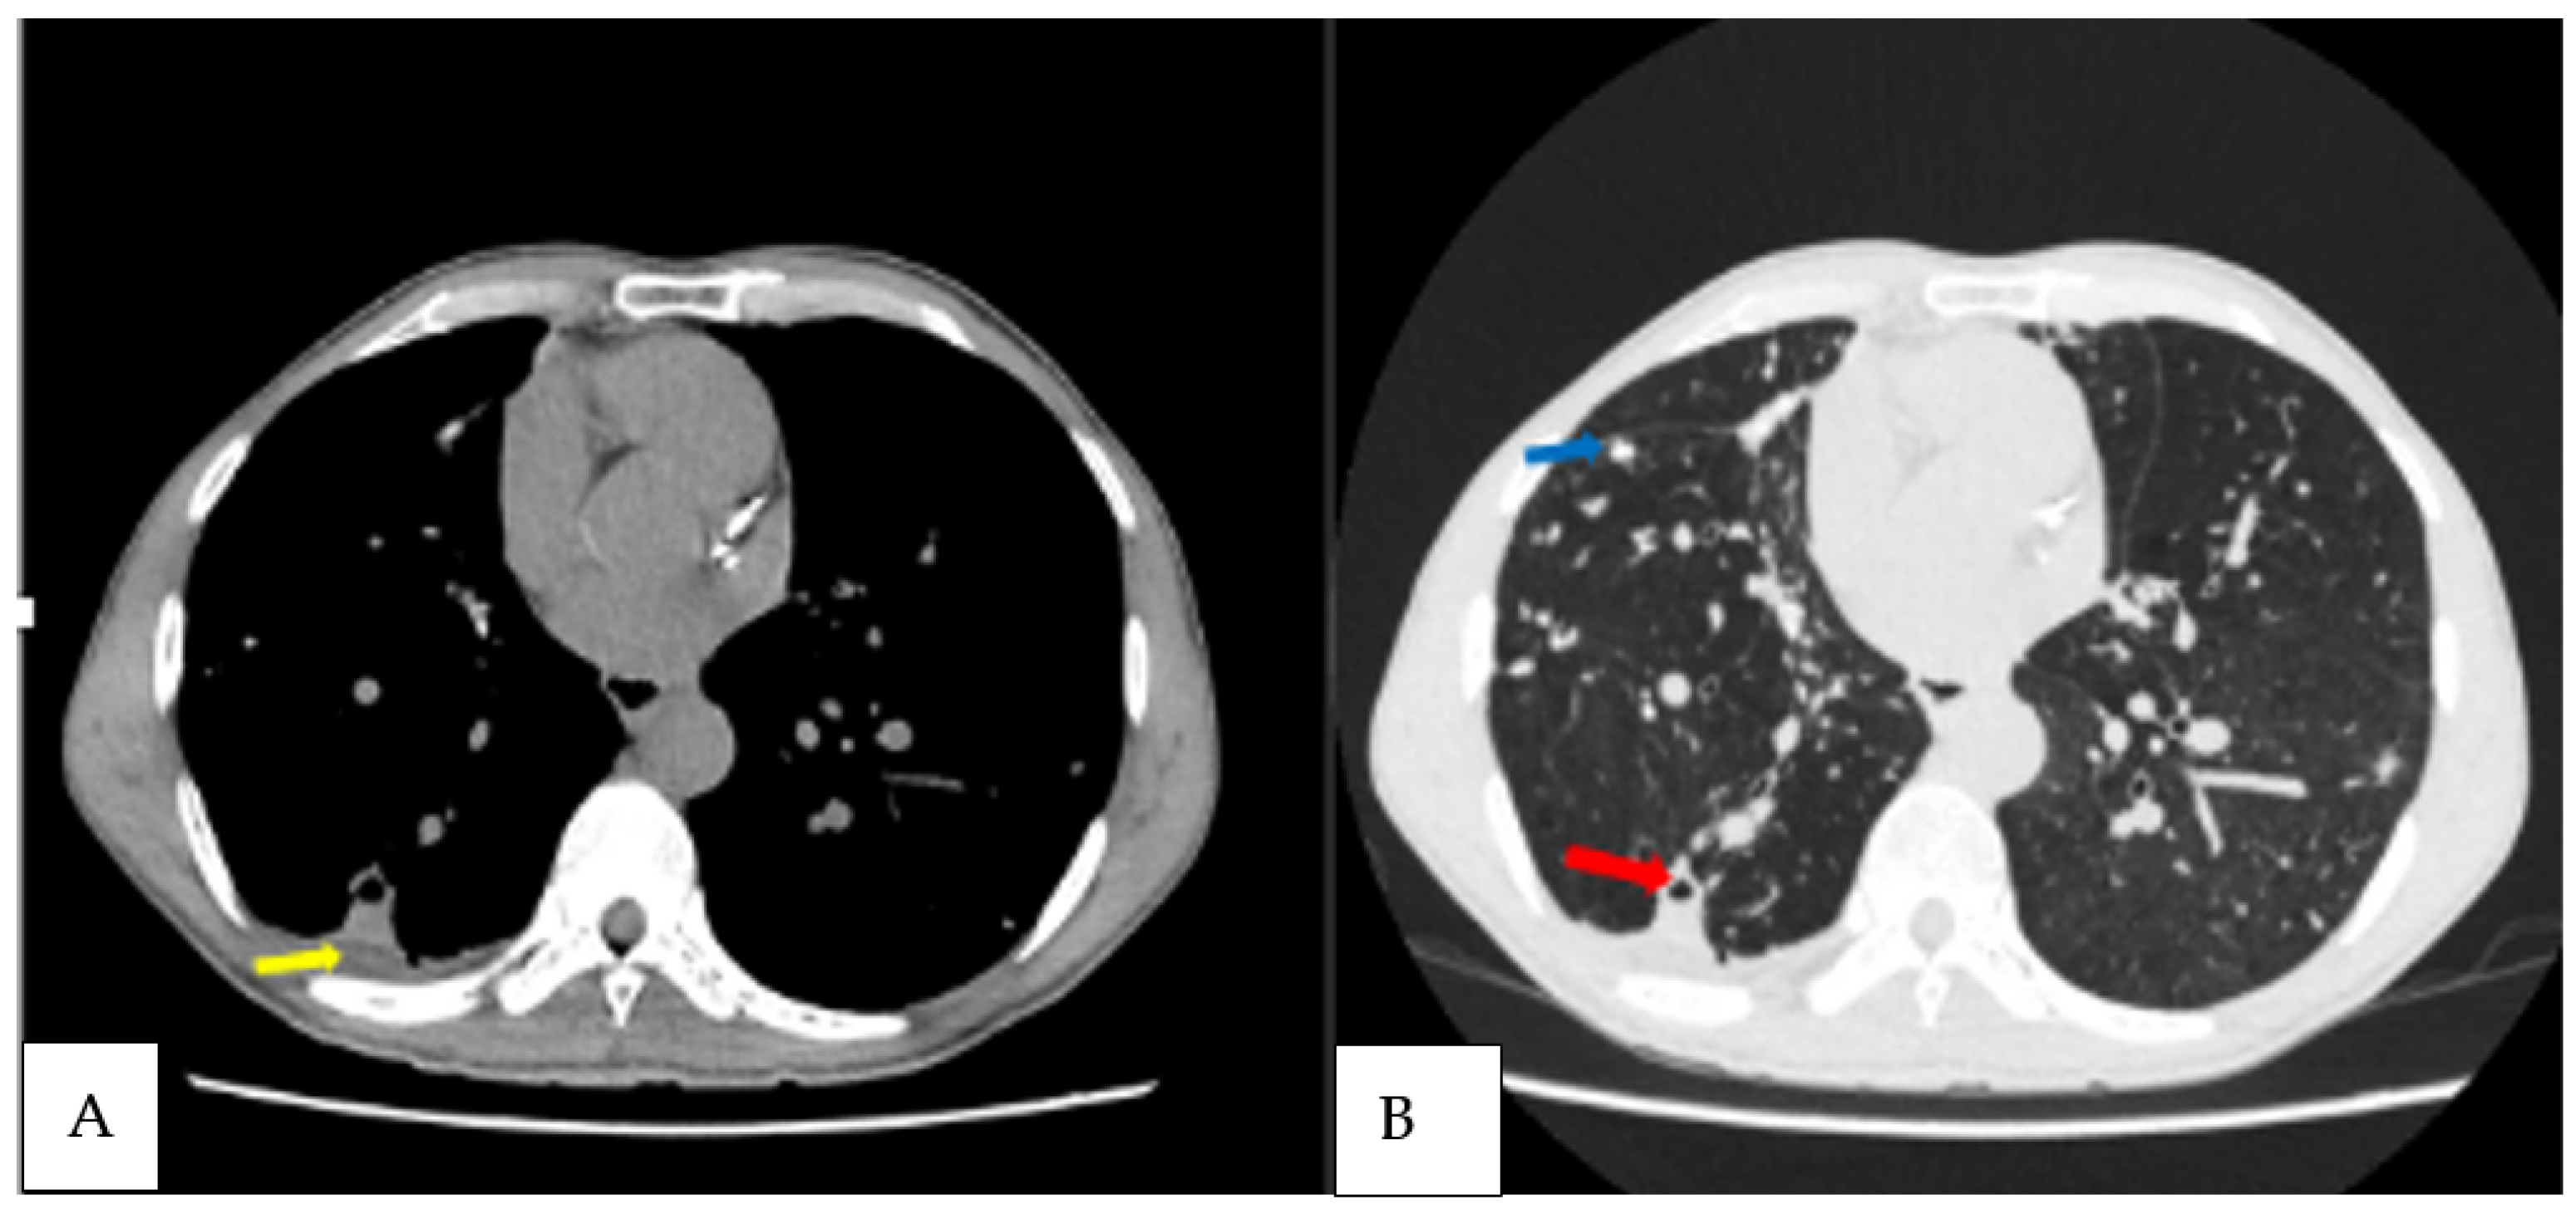

| 30 | M | Cough, haemoptysis, chest pain, weight loss | Positive | A. fumigatus, A. niger | Cavities, intracavitary material, pericavitary infiltration, pleural thickening adjacent cavity, bronchiectasis, pleural effusion | 45, 29, 83 |

| 49 | M | Cough, dyspnoea, weight loss | Positive | A. fumigatus | Cavities, fungal ball, pleural thickening adjacent cavity, pericavitary fibrosis, bronchiectasis | 46, 14, 23 |

| 50 | M | Haemoptysis, cough, fatigue | Positive | A. fumigatus | Cavities, intracavitary material, pleural thickening adjacent cavity, pericavitary fibrosis, nodules, bronchiectasis | 30, 15, 49 |